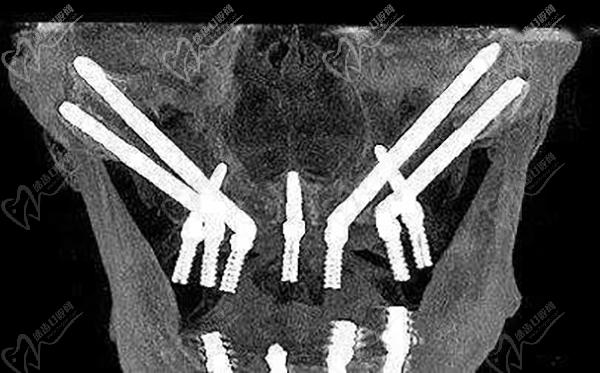

全口種植牙穿顴種植

即使是全口無(wú)牙頜種植牙,上下牙頜多顆牙齒缺失、烤瓷牙壞掉、高齡疑難無(wú)骨種植牙等等,都是可以通過(guò)先進(jìn)的種植牙技術(shù)來(lái)解決的。